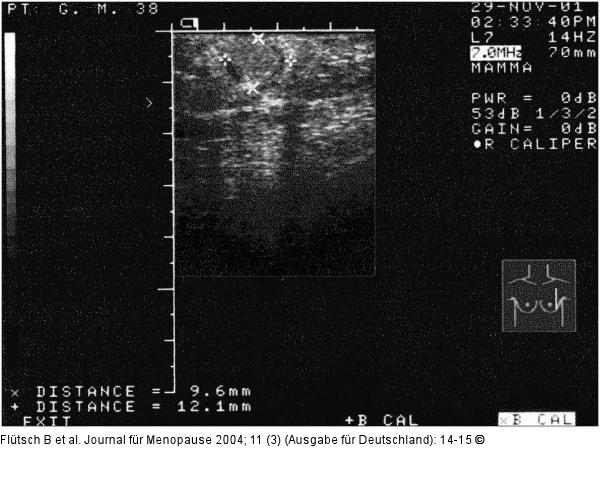

Abbildung 1: Mammographie - Knoten Mammasonographie vom November 2001 |